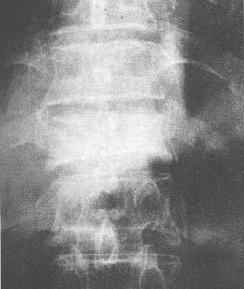

转移性骨肿瘤(成骨型)

前列腺癌胸椎转移(成骨型)。第11胸椎椎体均匀致密呈象牙质样,椎体略压缩变扁,椎间隙正常。